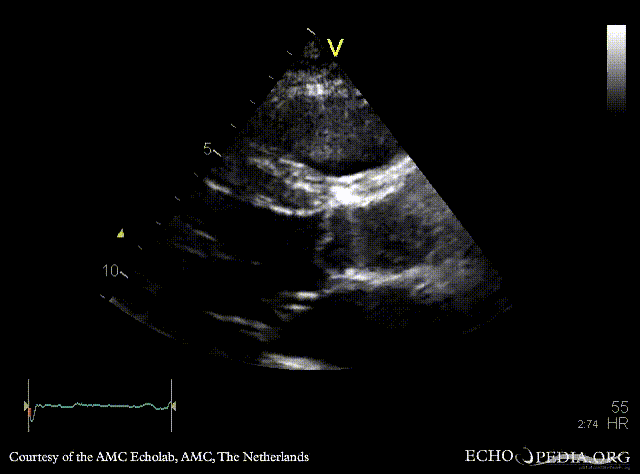

Davids procedure

Courtesy of: AMC Echolab, AMC, The Netherlands

PLAX: native aortic valve and prosthesis in ascending aorta PLAX with Color Doppler